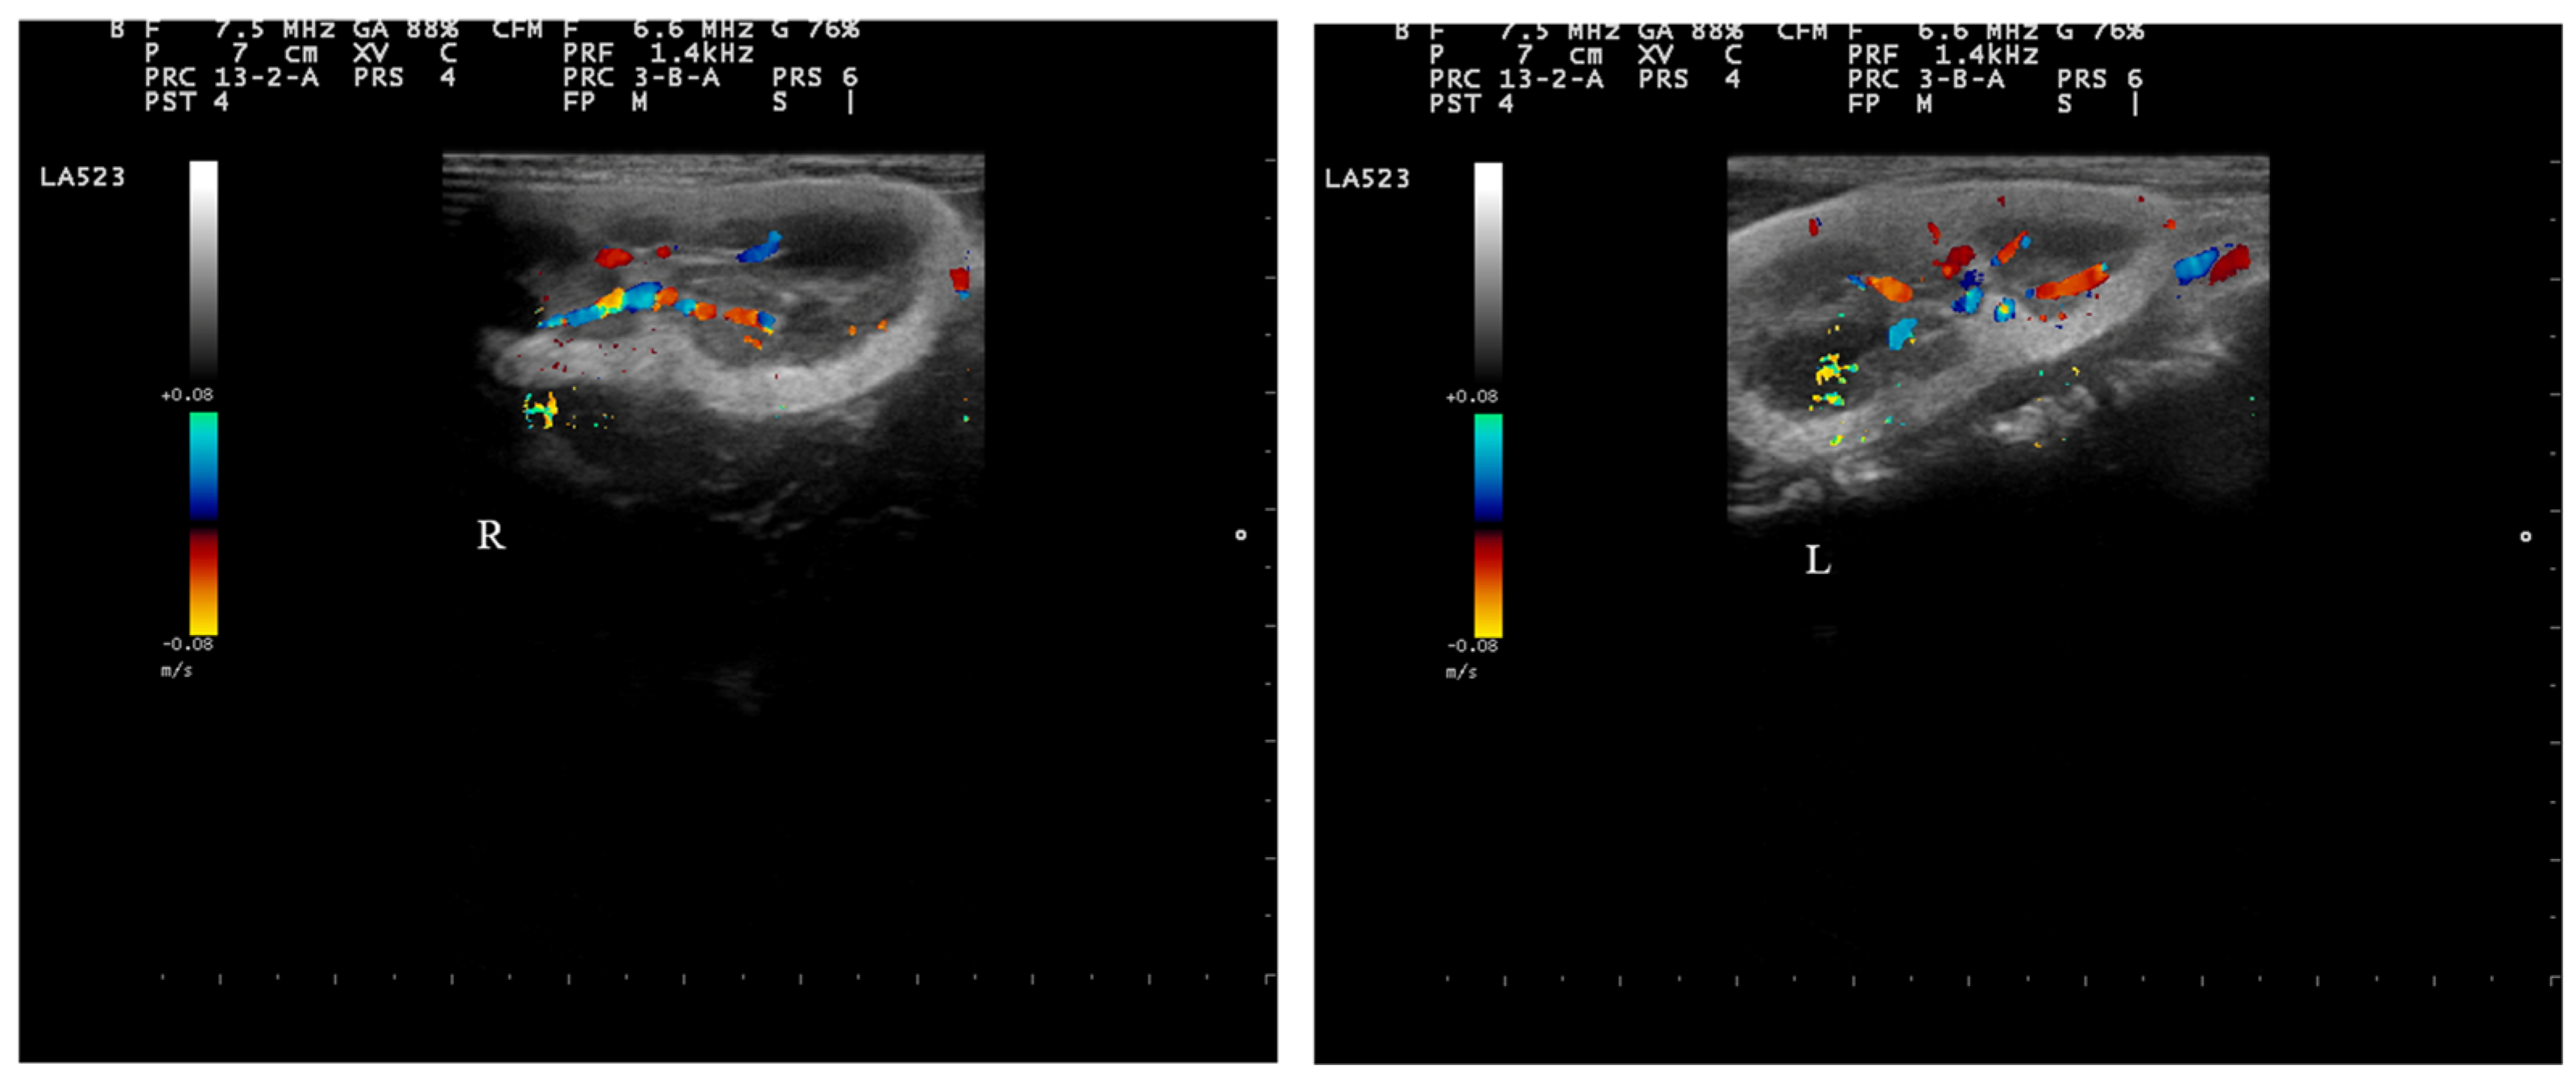

2.4. Doppler Examination